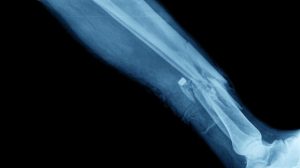

Memahami Patah Tulang dan Jenisnya

Patah tulang merupakan kejadian tulang yang mengalami benturan atau terjatuh dan berimbas pada tulang patah, retak, pecah atau berubah dari posisi semula. Penyebab patah tulang yang umum terjadi antara lain kecelakaan lalu lintas, salah melakukan teknik olahraga, terjatuh dari ketinggian, dan lain sebagainya. Biasanya benturan keras yang terjadi membuat tulang mengalami kondisi seperti ini, kecuali tulang orang yang berusia tua bisa mengalami patah tulang karena faktor osteoporosis. Dibagi dalam beberapa kelompok, berikut merupakan jenis patah tulang yang perlu dipahami:

• Patah tulang tertutup

Merupakan kondisi patah tulang yang dialami seseorang terjadi di bagian dalam atau tidak merobek kulit.

• Patah tulang terbuka

Merupakan kondisi patah tulang yang mengakibatkan robekan pada kulit sehingga Anda bisa melihat tulang di lapisan dalamnya.

• Patah tulang tidak lengkap

Merupakan kondisi patah tulang yang hanya menyebabkan retak atau tidak membagi tulang menjadi dua bagian sesuai dengan tipe masing-masing yaitu hairline fracture atau retak yang tipis, greenstick fracture atau salah satu sisi tulang alami retak, buckle atau torus fracture dimana tulang yang patah tidak memisahkan dua sisi tulang, kecuali pada bagian yang retak lebih menonjol.

• Patah tulang lengkap

Merupakan kondisi patah tulang yang mengakibatkan tulang patah menjadi dua bagian atau lebih, dan terbagi menjadi beberapa jenis seperti single fractures, comminuted fractures, compression fracture, dan lain-lain.  Kecelakaan atau tertimpa benda berat bisa membuat tingkat keparahan patah tulang semakin tinggi. Tekanan yang semakin besar juga akan membuat risiko Anda alami patah tulang skala berat bisa terjadi sehingga butuh waktu lama untuk pemulihan. Adapun kasus patah tulang yang umum terjadi bisa sembuh dengan bantuan fisioterapis handal. Fisioterapi patah tulang akan membantu Anda melakukan perawatan dan pemulihan sesuai dengan kondisi pasien.